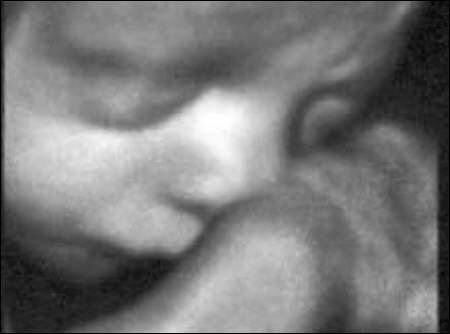

Aufgrund einer hohen technischen Ausstattung in meiner Ordination ist es mir möglich ein dreidimensionales Bild von Ihrem Kind anzufertigen. Die Kindsbewegungen können „live“ am Bildschirm mitverfolgt werden (4D).

Dieses ermöglicht einerseits die bessere Diagnostik einiger Fehlbildungen wie etwa der Lippen-Kiefer-Gaumenspalte, andererseits kann so das erste "Foto" von Ihrem noch ungeborenen Kind gemacht werden, was die Mutter-Kind-Beziehung zusätzlich fördert und sicherlich eine nette Erinnerung an diese außergewöhnliche Zeit ist.